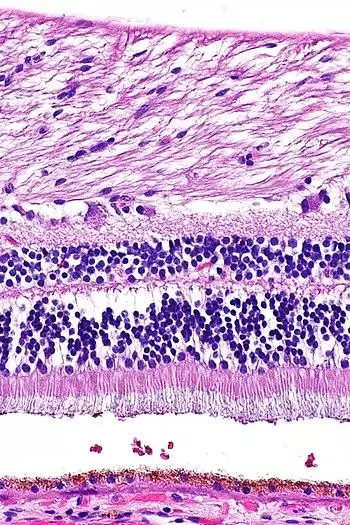

Retina (part of the eye) stained with hematoxylin and eosin, cell nuclei stained blue-purple and extracellular material stained pink.

H&E is the combination of two histological stains: hematoxylin and eosin. The hematoxylin stains cell nuclei blue, and eosin stains the extracellular matrix and cytoplasm pink, with other structures taking on different shades, hues, and combinations of these colors.[5][6] The stain shows the general layout and distribution of cells and provides a general overview of a tissue sample's structure.[7] Hence a pathologist can easily differentiate between the nuclear and cytoplasmic parts of a cell.

Hematoxylin principally colors the nuclei of cells blue or dark-purple,[6][15][14] along with a few other tissues, such as keratohyalin granules and calcified material. Eosin stains the cytoplasm and some other structures including extracellular matrix such as collagen[5][7][14] in up to five shades of pink.[8] The eosinophilic (substances that are stained by eosin)[5] structures are generally composed of intracellular or extracellular proteins. The Lewy bodies and Mallory bodies are examples of eosinophilic structures. Most of the cytoplasm is eosinophilic and is rendered pink.[10][15] Red blood cells are stained intensely red.